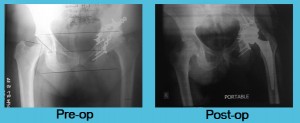

Total HIP Replacement Revision of Metal on Metal THR due to Pseudotumor formation

39 years old gentleman is a follow up case of right total hip replacement (Large Diameter head – Metal on Metal) done 5 years back for healed tuberculosis of hip. Now patient has presented with complains of pain around right hip on walking.

Fresh x-rays showed radiolysis around acetabulum with no ... Read more..